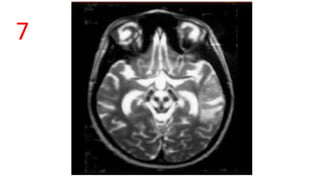

FACE OF GIANT PANDA

• T2 W , Wilson’s disease.

• EYES - High signal intensity in the Midbrain

tegmentum sparing the red nucleus

• EARS - Preservation of signal intensity of the lateral

portion of the pars reticulata of the substantia nigra.

• CHIN/MOUTH - Low signal intensity of the superior

colliculus

• Similar changes when seen in Pons – Face of Miniature

Panda / panda Cub Sign

• Together called as – Double Panda Sign.